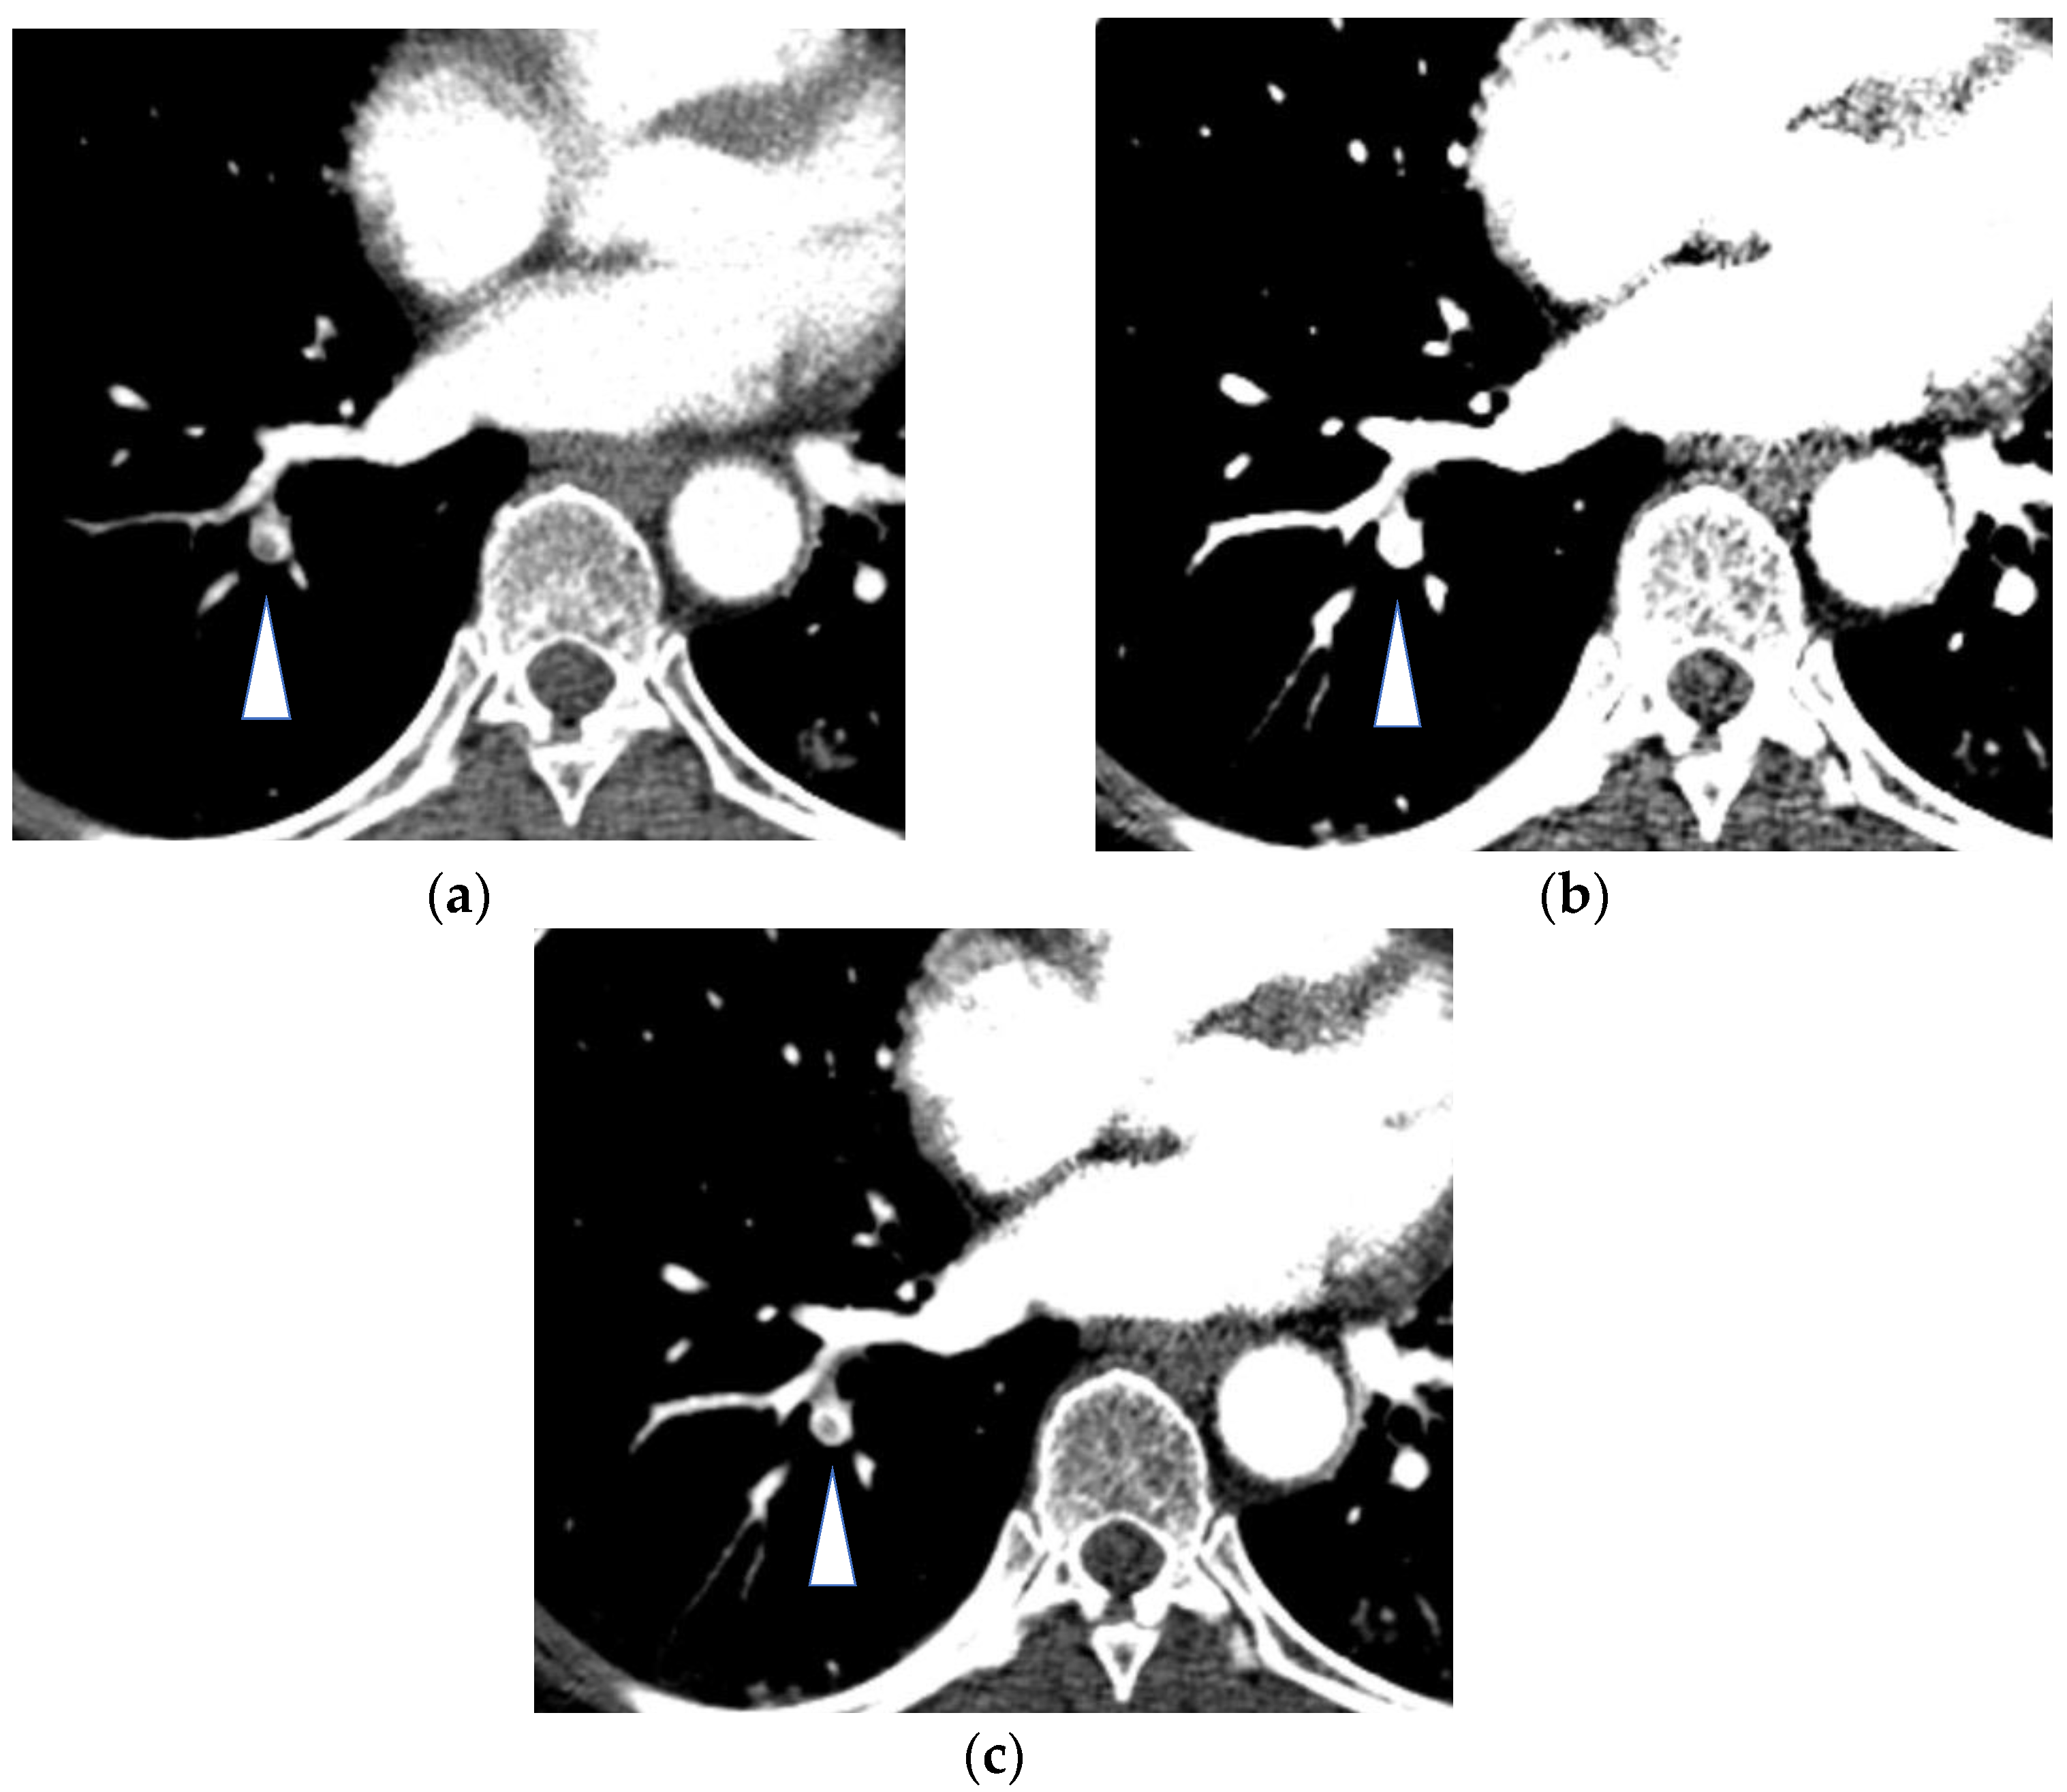

- Hasegawa, I.; Boiselle, P.M.; Hatabu, H. Bronchial artery dilatation on MDCT scans of patients with acute pulmonary embolism: Comparison with chronic or recurrent pulmonary embolism. AJR Am. J. Roentgenol. 2004, 182, 67–72. [Google Scholar] [CrossRef] [PubMed]

- Almeida, J.; Leal, C.; Figueiredo, L. Evaluation of the bronchial arteries: Normal findings, hypertrophy and embolization in patients with hemoptysis. Insights Imaging 2020, 11, 70. [Google Scholar] [CrossRef]

- Remy-Jardin, M.; Duhamel, A.; Deken, V.; Bouaziz, N.; Dumont, P.; Remy, J. Systemic collateral supply in patients with chronic thromboembolic and primary pulmonary hypertension: Assessment with multi-detector row helical CT angiography. Radiology 2005, 235, 274–281. [Google Scholar] [CrossRef] [PubMed]

- Mitzner, W.; Wagner, E.M. Vascular remodeling in the circulations of the lung. J. Appl. Physiol. 2004, 97, 1999–2004. [Google Scholar] [CrossRef] [Green Version]

- Hong, Y.J.; Kim, J.Y.; Choe, K.O.; Hur, J.; Lee, H.J.; Choi, B.W.; Kim, Y.J. Different perfusion pattern between acute and chronic pulmonary thromboembolism: Evaluation with two-phase dual-energy perfusion CT. AJR Am. J. Roentgenol. 2013, 200, 812–817. [Google Scholar] [CrossRef]

- Renard, B.; Remy-Jardin, M.; Santangelo, T.; Faivre, J.B.; Tacelli, N.; Remy, J.; Duhamel, A. Dual-energy CT angiography of chronic thromboembolic disease: Can it help recognize links between the severity of pulmonary arterial obstruction and perfusion defects? Eur. J. Radiol. 2011, 79, 467–472. [Google Scholar] [CrossRef]

- Bacon, J.L.; Madden, B.P.; Gissane, C.; Sayer, C.; Sheard, S.; Vlahos, I. Vascular and Parenchymal Enhancement Assessment by Dual-Phase Dual-Energy CT in the Diagnostic Investigation of Pulmonary Hypertension. Radiol. Cardiothorac. Imaging 2020, 2, e200009. [Google Scholar] [CrossRef]